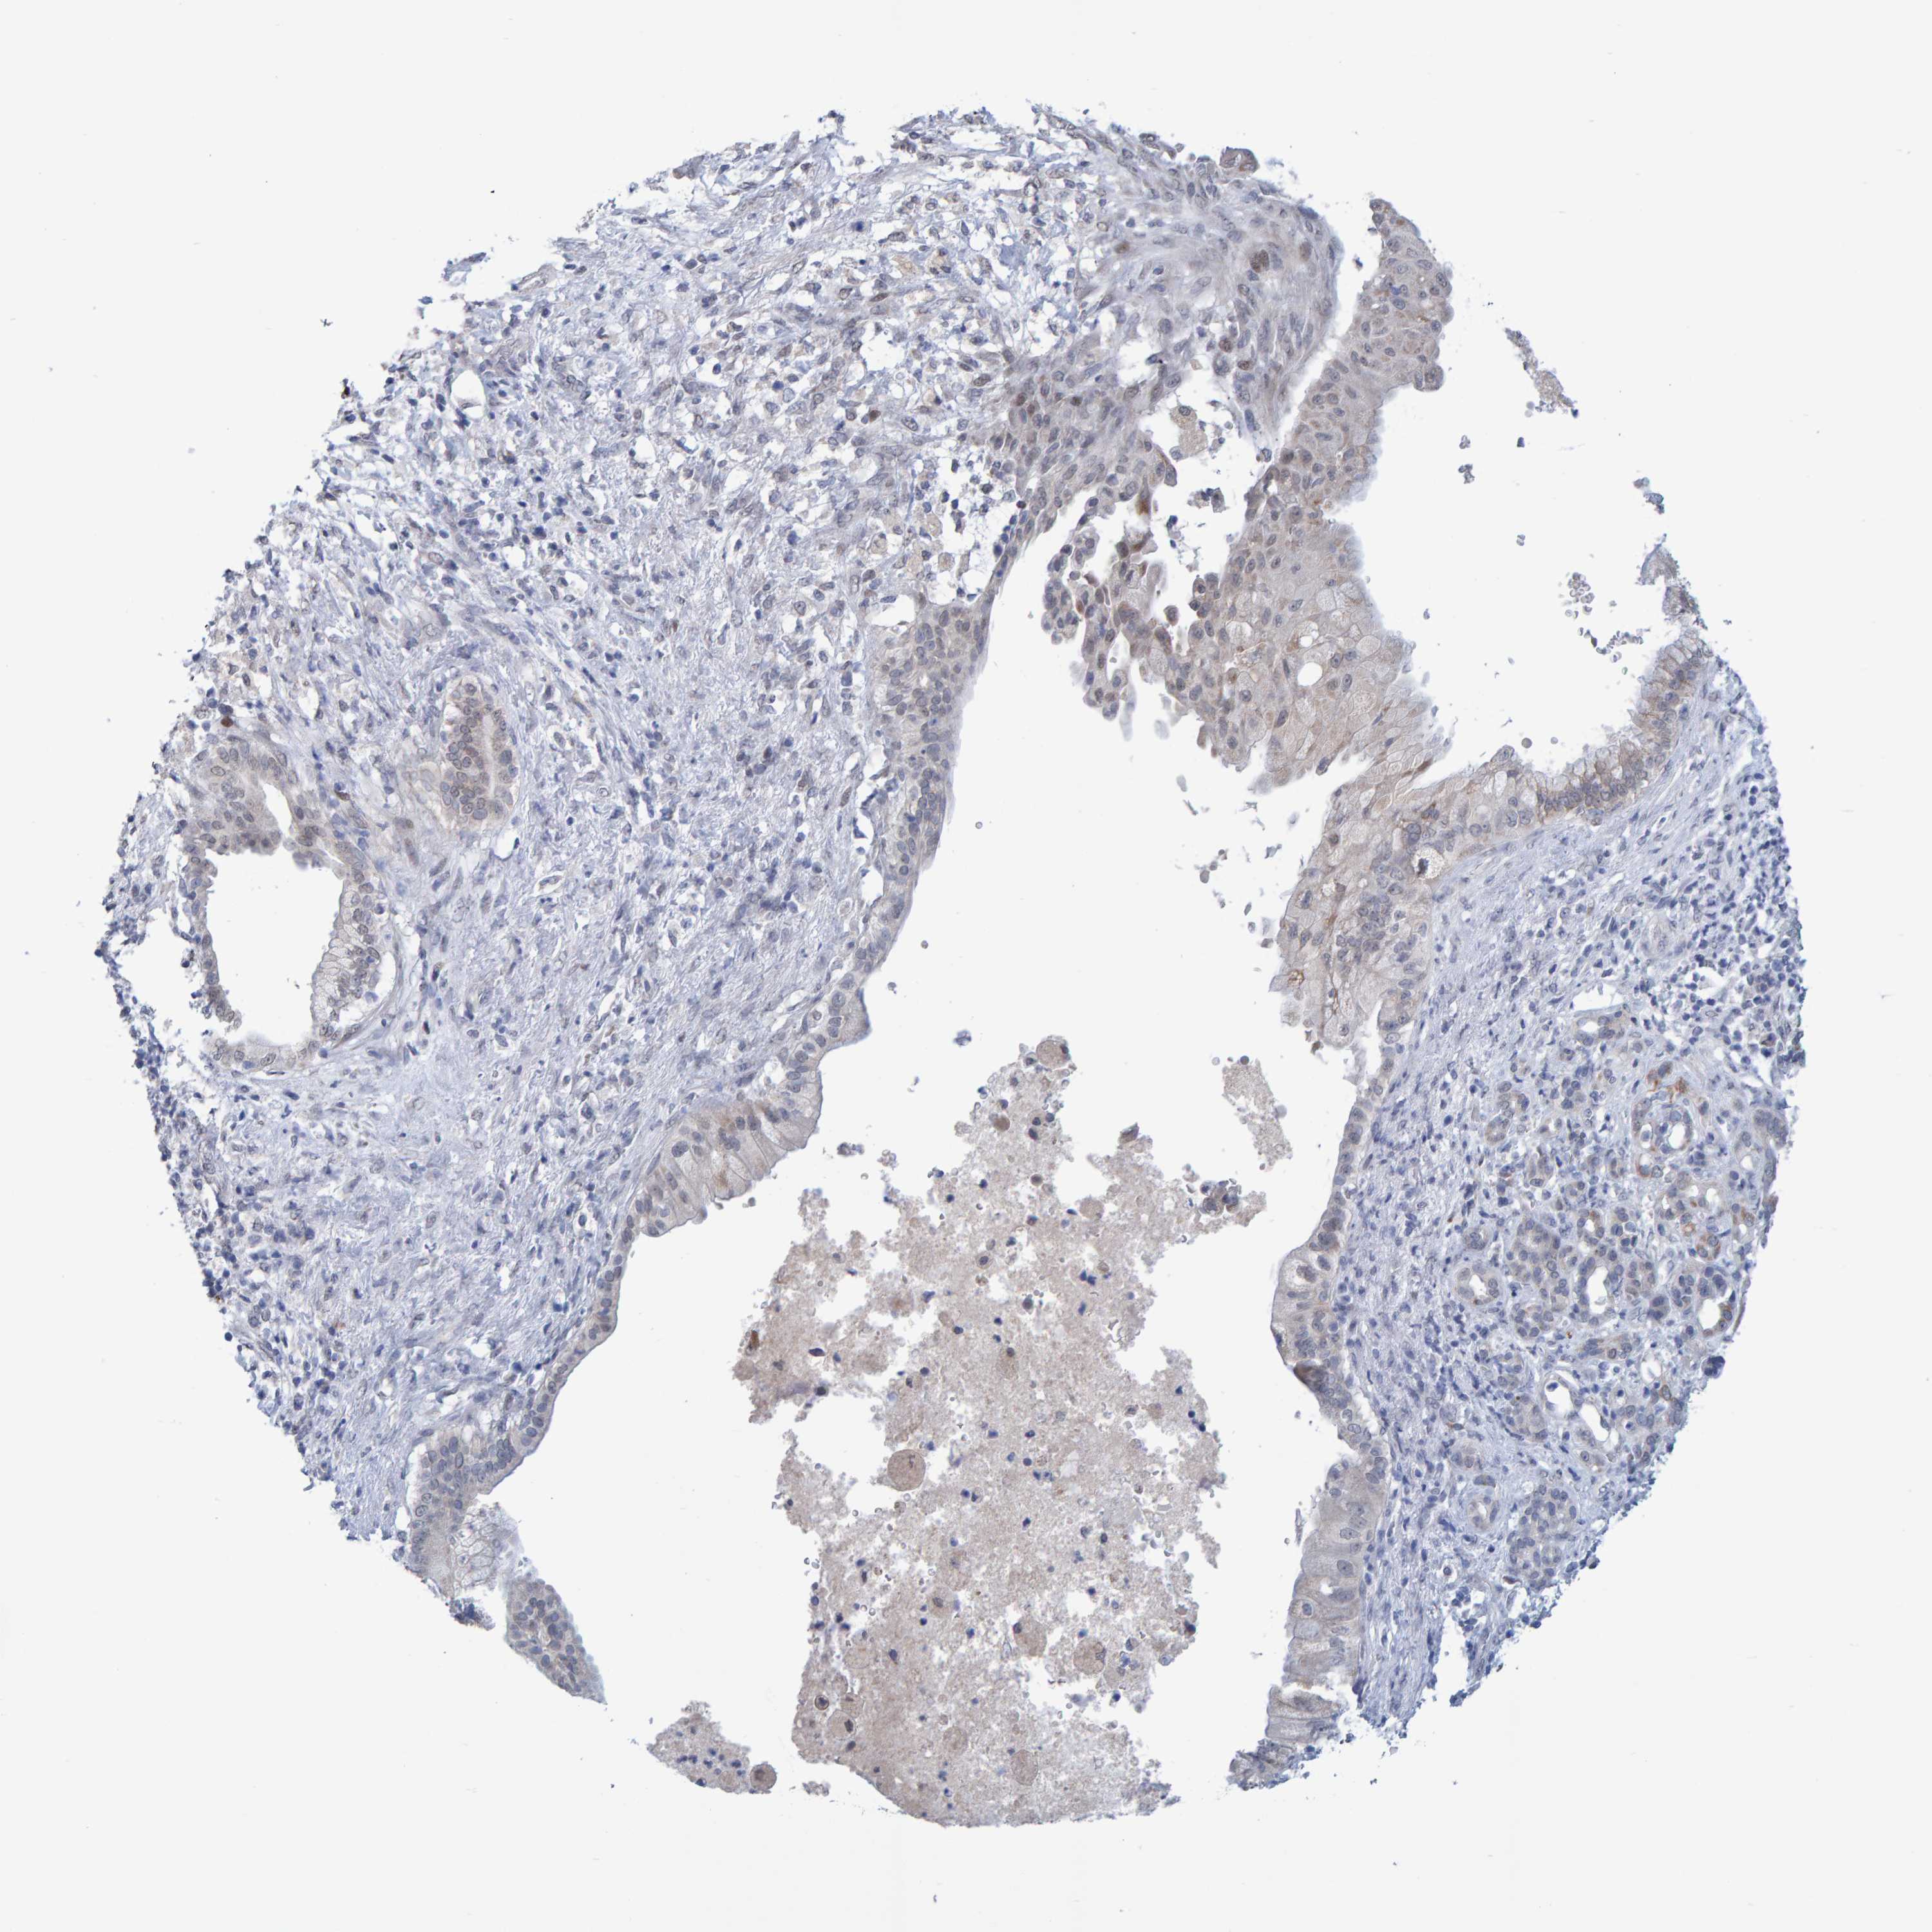

PANCREATIC CANCER - Protein expressioni

A mouse-over function shows sample information and annotation data. Click on an image to view it in a full screen mode. Samples can be filtered based on level of antibody staining by selecting one or several of the following categories: high, medium, low and not detected. The assay and annotation is described here.

Note that samples used for immunohistochemistry by the Human Protein Atlas do not correspond to samples in the TCGA dataset.

Antibody stainingi

Antibody staining in the annotated cell types in the current human tissue is reported as not detected, low, medium, or high, based on conventional immunohistochemistry profiling in selected tissues. This score is based on the combination of the staining intensity and fraction of stained cells.

Each image is clickable and will lead to virtual microscopy that enables deeper exploration of all samples and also displays staining intensity scores, fraction scores and subcellular localization as well as patient and tissue information for each sample.

Antibody HPA023389

Antibody HPA027762

Staining

High

Medium

Low

Not detected

Intensity

Strong

Moderate

Weak

Negative

Quantity

>75%

75%-25%

<25%

None

Location

Nuclear

Cytoplasmic/membranous

Cytoplasmic/membranous,nuclear

Adenocarcinoma, NOS